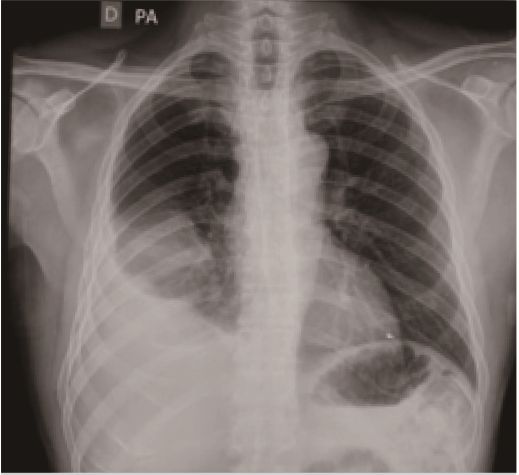

Although the referring facility did not provide endoscopic or radiologic images from the first intervention, a thoracic x-ray performed by São Paulo showed the previous SEMS

in place (Figures 1 and 2).